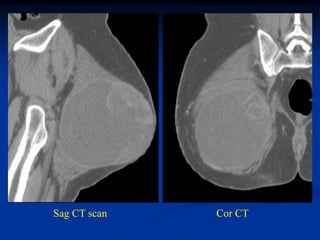

Case #1203.1   Pleomorphic liposarcoma      Axial CT scan

65 year male with recent onset buttock tumor mass in area of previous

resected large benign lipoma 6 years ago

Sag CT scan   Cor CT

Axial T-1     T-2

fluid

tumor

Gad

Sag T-2   Surgical specimen

Case #1203.1 Pleomorphic liposarcoma Axial CT scan 65 year male with recent onset buttock tumor mass in area of previous resected large benign lipoma 6 years ago

Axial T-1 T-2 fluid tumor Gad